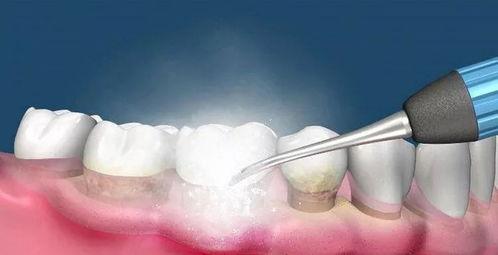

比如,有一个视频里,洗牙师用一把类似刷子的工具,轻轻地刷过牙齿表面,然后又用一个小小的超声波仪器,把牙结石震碎。看着那些牙结石像小石头一样被震落,真是让人心情愉悦啊!